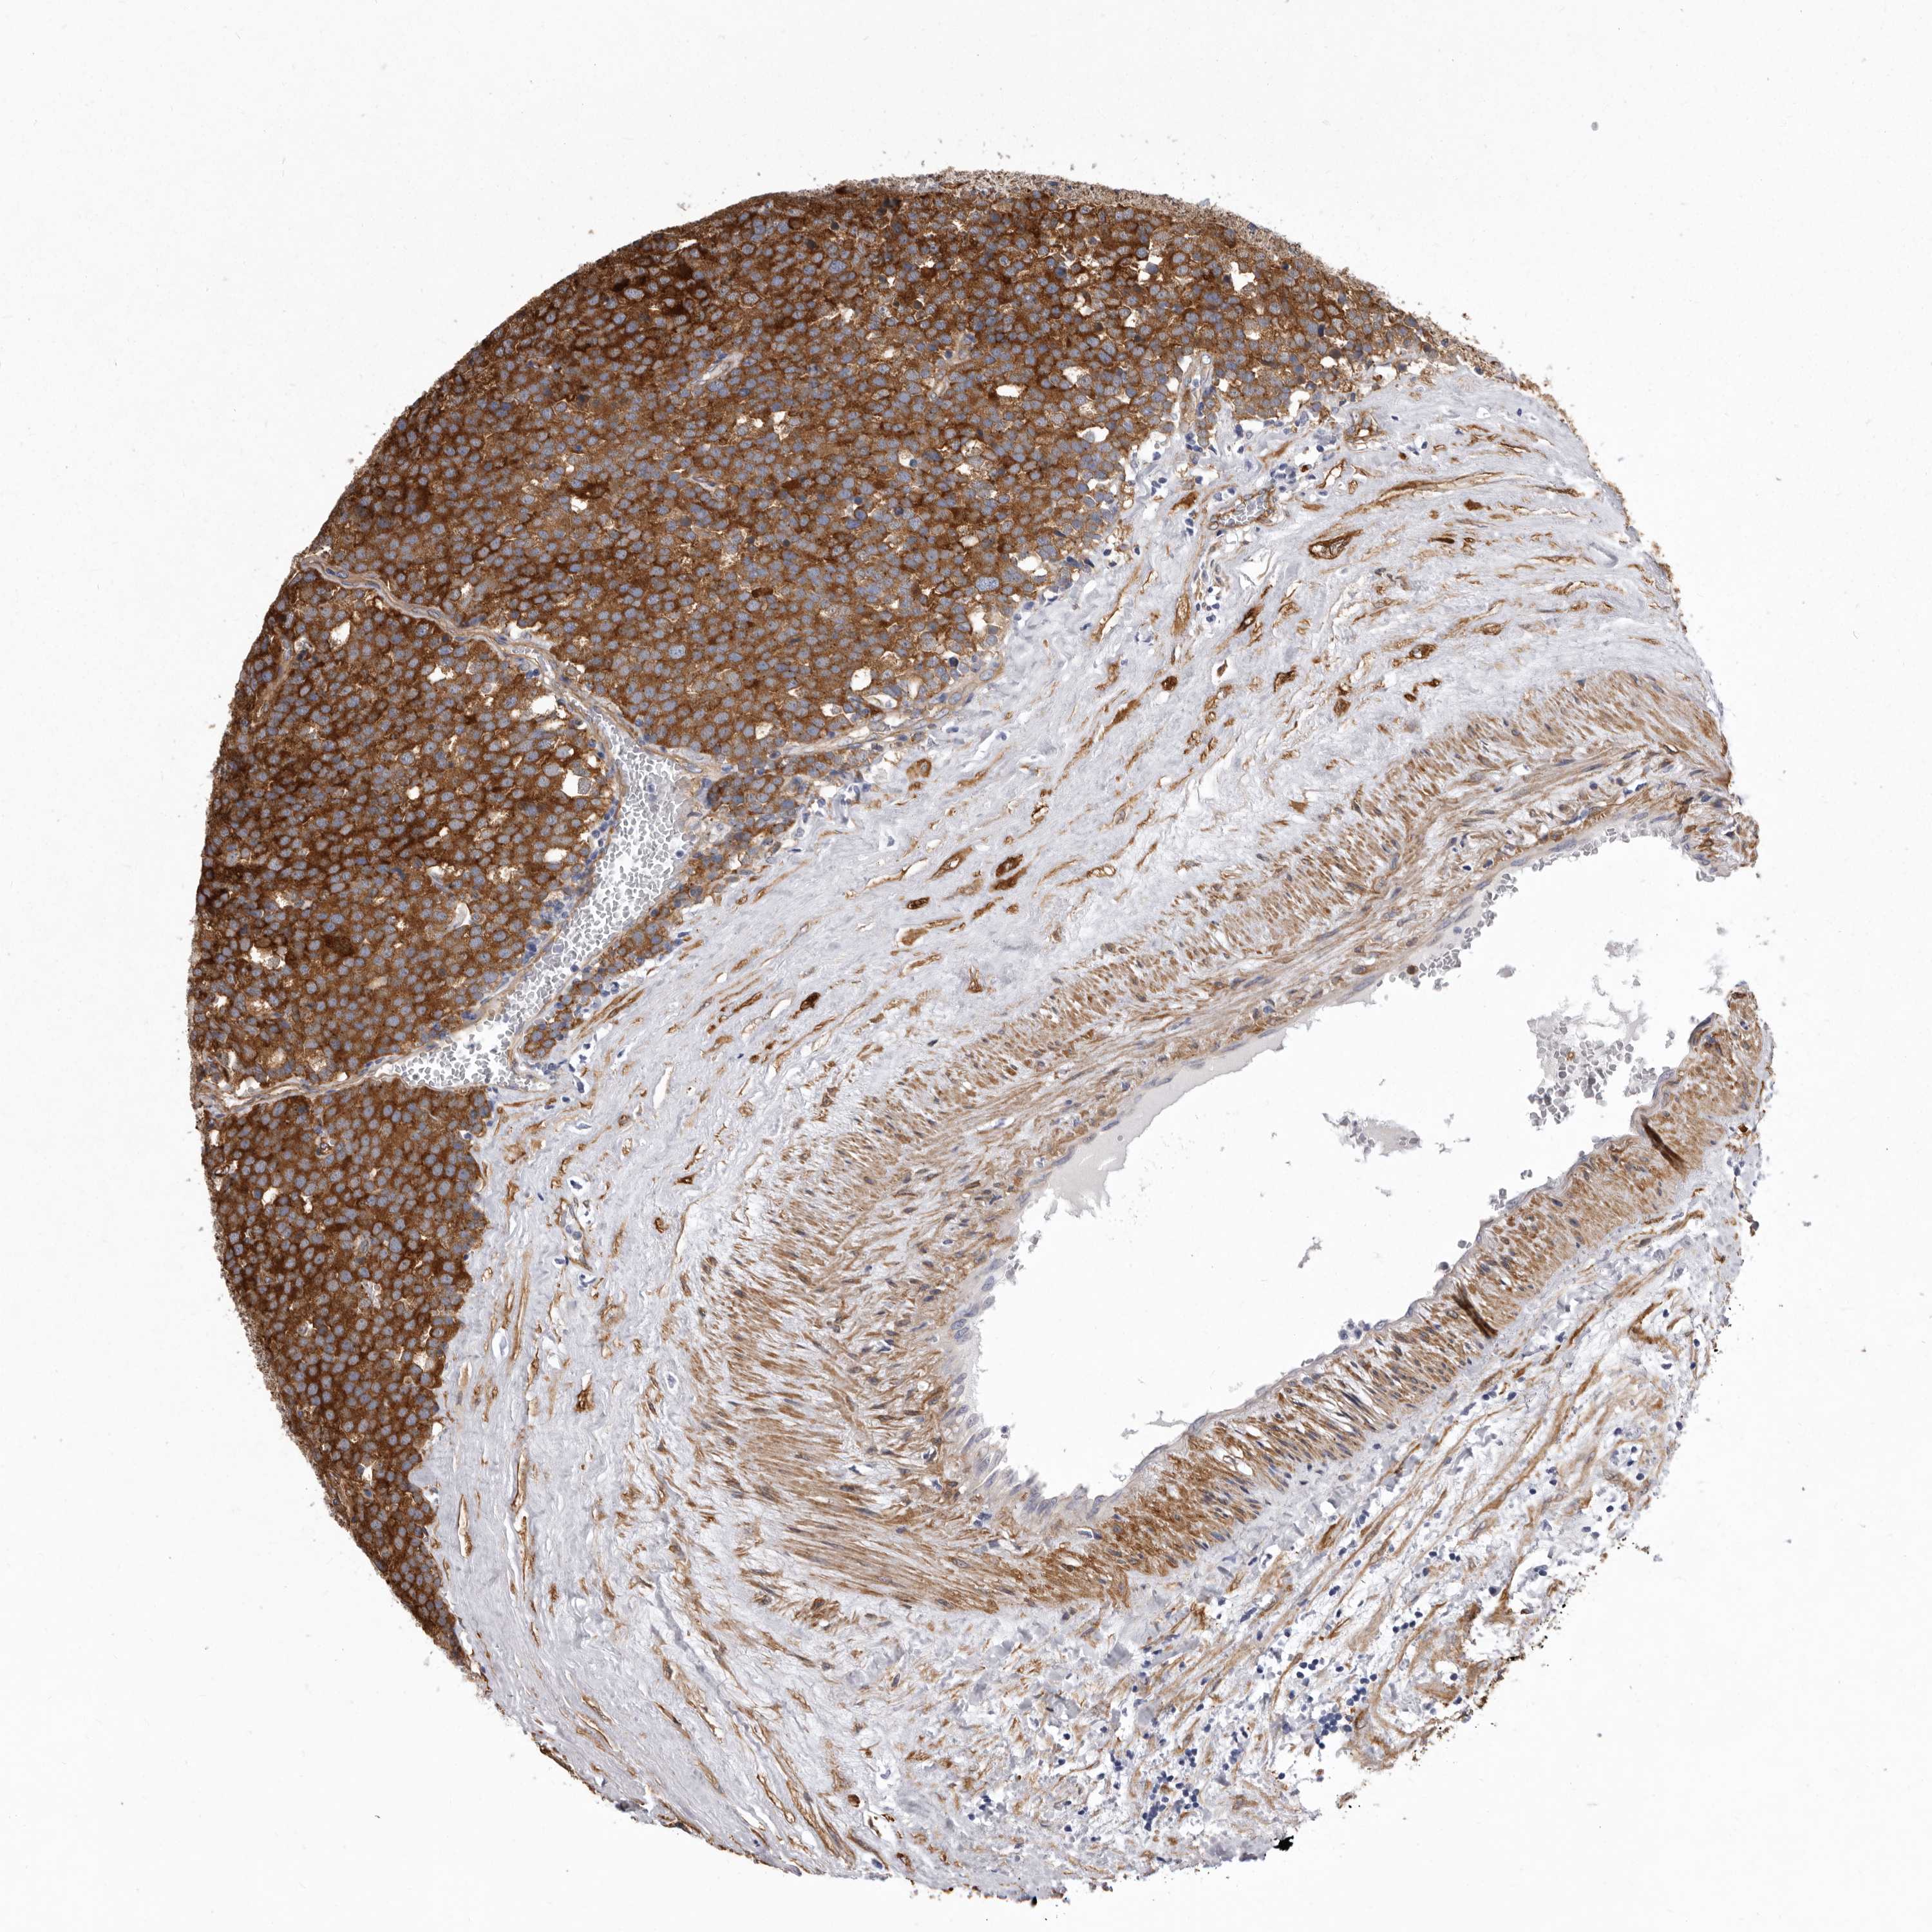

TESTIS CANCER - Protein expressioni

A mouse-over function shows sample information and annotation data. Click on an image to view it in a full screen mode. Samples can be filtered based on level of antibody staining by selecting one or several of the following categories: high, medium, low and not detected. The assay and annotation is described here.

Note that samples used for immunohistochemistry by the Human Protein Atlas do not correspond to samples in the TCGA dataset.

Antibody stainingi

Antibody staining in the annotated cell types in the current human tissue is reported as not detected, low, medium, or high, based on conventional immunohistochemistry profiling in selected tissues. This score is based on the combination of the staining intensity and fraction of stained cells.

Each image is clickable and will lead to virtual microscopy that enables deeper exploration of all samples and also displays staining intensity scores, fraction scores and subcellular localization as well as patient and tissue information for each sample.

Antibody HPA028448

Staining

High

Medium

Low

Not detected

Intensity

Strong

Moderate

Weak

Negative

Quantity

>75%

75%-25%

<25%

None

Location

Nuclear

Cytoplasmic/membranous

Cytoplasmic/membranous,nuclear

Carcinoma, Embryonal, NOS

Seminoma, NOS